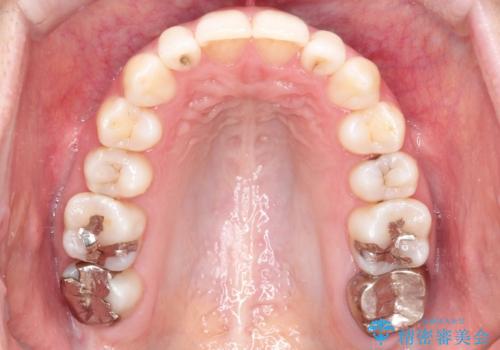

初診時の歯並びの状態としては、上下ともに前歯部の中等度のがたつきがあり、特に左上の前歯が1本内側に入り込んでしまっている状態でした。

また、2mm程度の正中離開がありました。

抜歯なし/インビザラインによるマウスピース矯正にて治療を行いました。